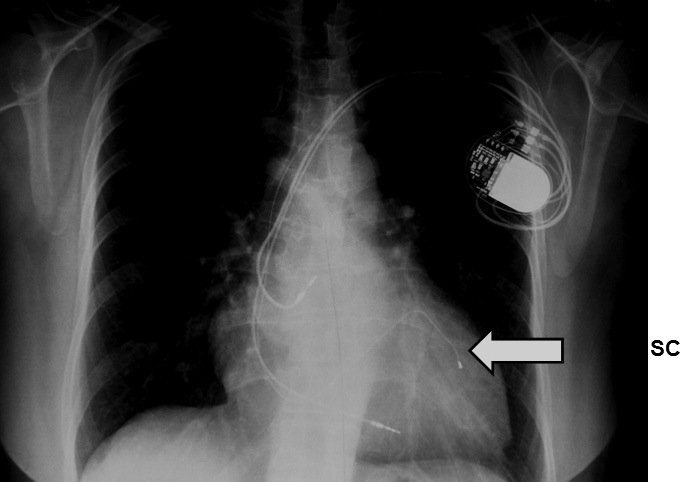

El implante de un MP para TRV requiere de un electrodo convencional en VD, el que es recomendable insertarlo en la región septal alta, y otro especialmente diseñado para estimular en la región basal de la pared lateral o póstero lateral del VI. A estas zonas se accede a través del SC desde donde el electrodo se avanza a una rama venosa lateral o póstero lateral del VI (Figura 2). Adicionalmente, si el paciente mantiene ritmo sinusal se inserta un electrodo auricular convencional en la aurícula derecha, y en el caso de los enfermos en FA permanente sólo se insertan los electrodos ventriculares. Los electrodos implantados se conectan a un MP especialmente diseñado, el que tiene canales separados para VD y VI, lo que permite estimular en ambos ventrículos en forma diferenciada según los requerimientos de cada paciente. Esto se define posterior al implante, midiendo mediante distintos métodos ecocardiográficos el grado de retardo entre septum y la pared lateral del VI. El MP se programa adelantando la estimulación en el canal del VI hasta que no exista retardo o se minimice al máximo. Así se corrige el retardo eléctrico y mecánico de la contracción ventricular izquierda – es decir se sincroniza- lo que produce mejoría de los parámetros de la función sistólica y diastólica del VI y disminuye el reflujo mitral, sin aumentar el consumo de O2 miocárdico 5 . En el ECG el cambio es inmediato, observándose que el QRS se angosta y aparece una onda Q en las derivaciones laterales y onda R en VI, como producto de la estimulación desde la región lateral del VI (Figuras 3 y 4), lo que difiere de la estimulación exclusiva desde ventrículo derecho, en que hay un patrón QS en las derivaciones precordiales derechas y QRS habitualmente positivo en precordiales izquierdas, además de un eje eléctrico izquierdo

Figura 2 Radiografía de un paciente portador de un marcapaso para terapia de resincronización ventricular. La flecha señala el electrodo que estimula el ventrículo izquierdo a través del seno coronario.